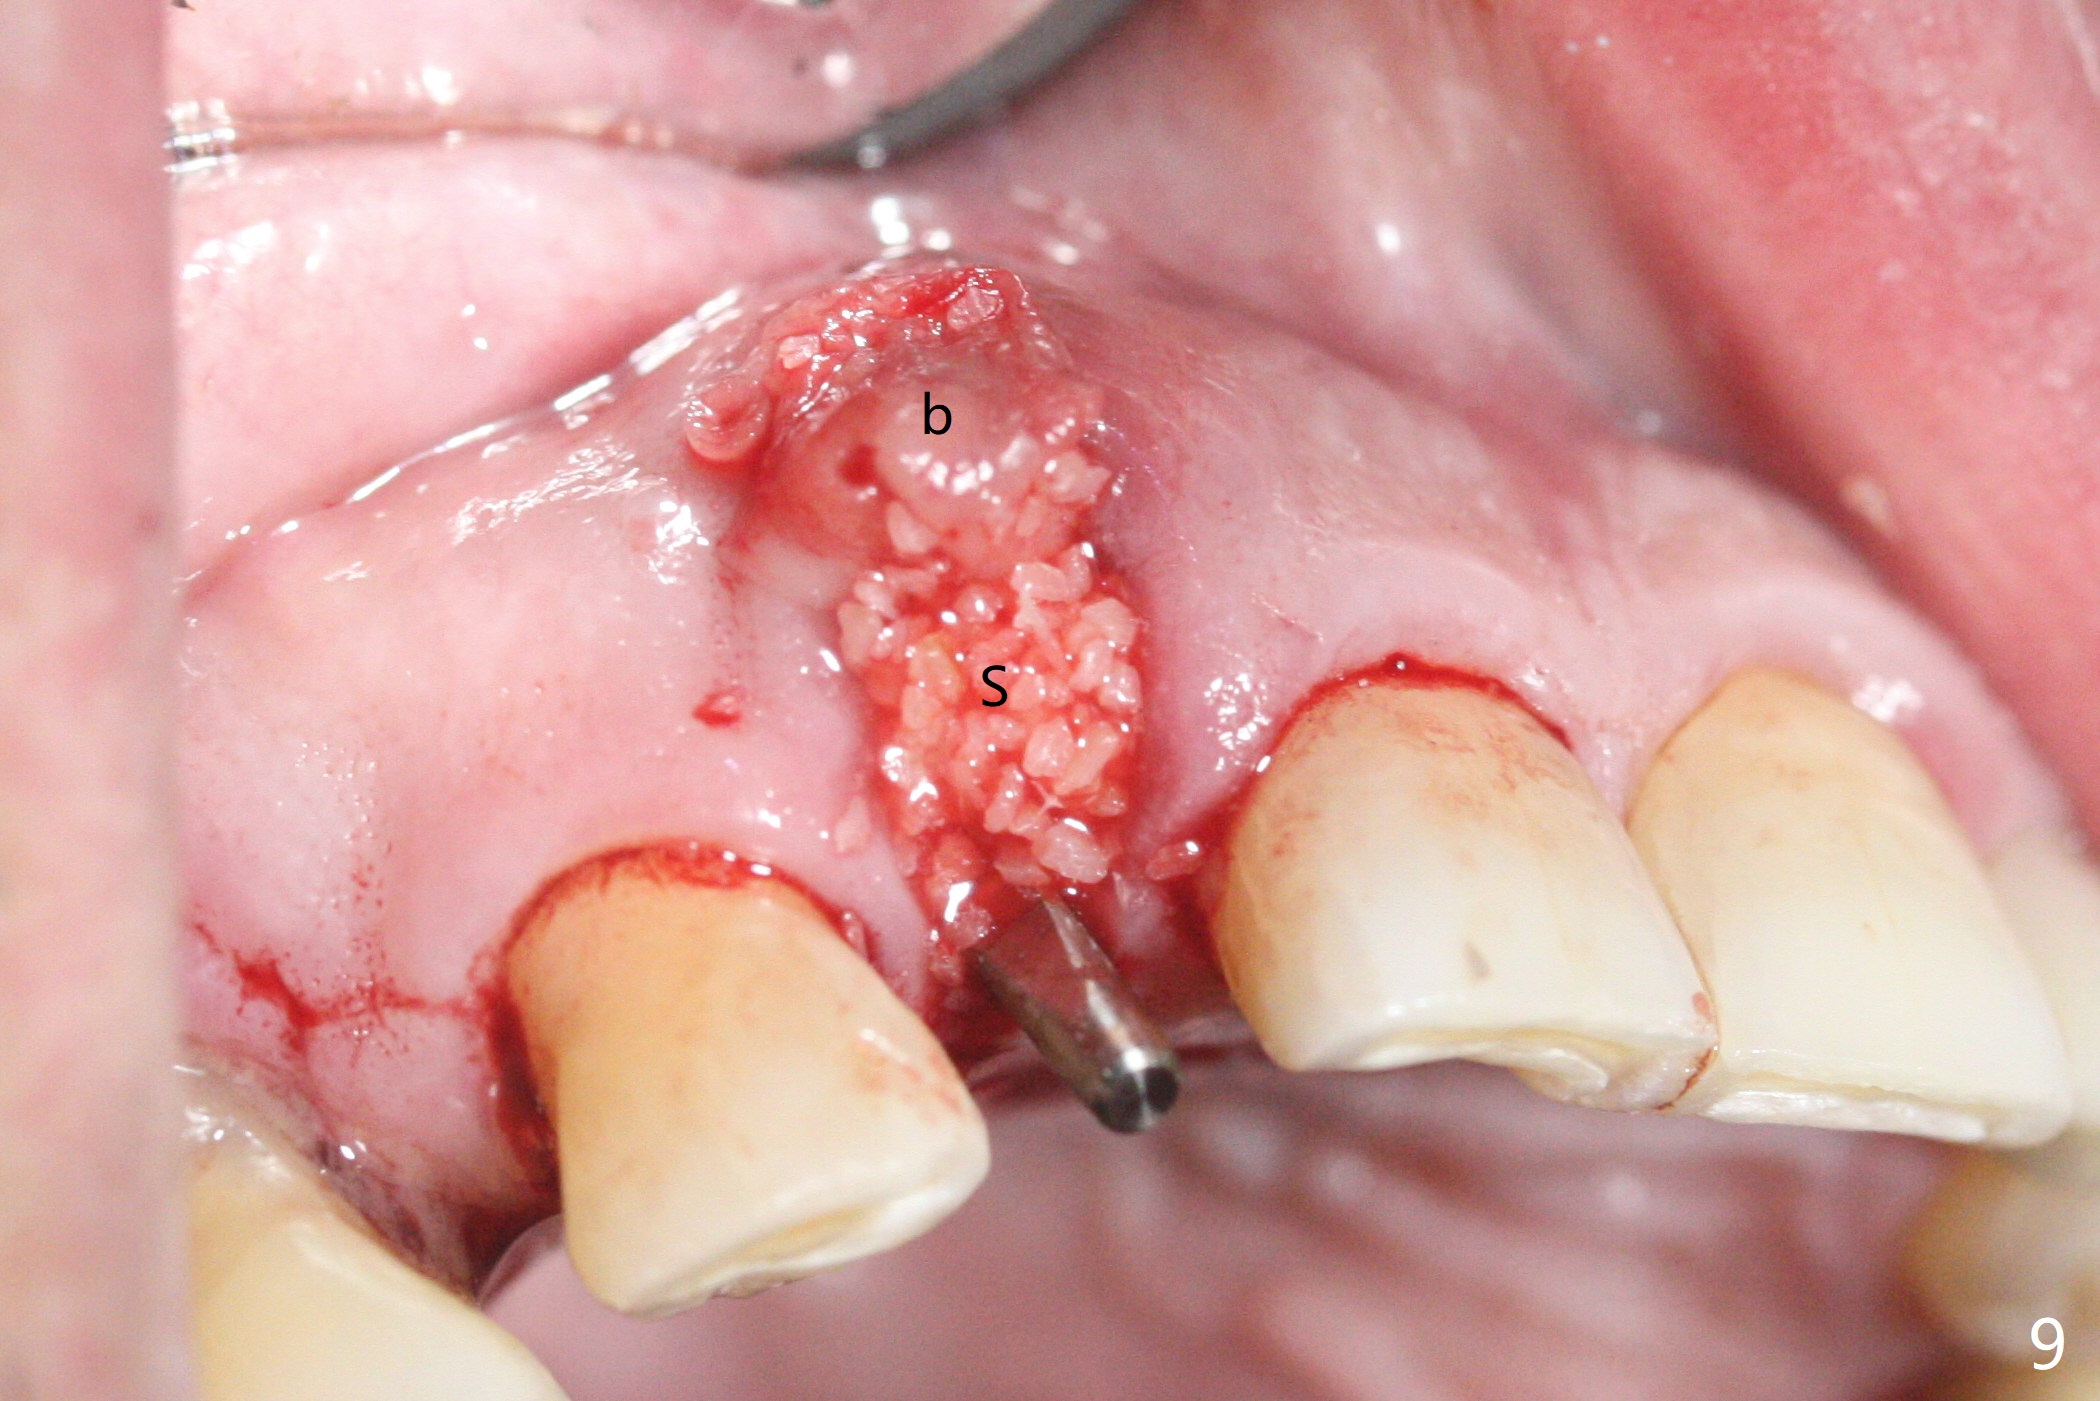

68岁男士右上2严重骨质吸收,颊侧骨板缺失,术前牙龈退缩也十分明显(图一,二),术中对脆弱牙龈缘(图三:*)不应施加任何压力或者牵拉,更不能切开,保持最佳血供。按照术前设计,在牙槽窝腭侧钻洞(图四),植入2.5x15毫米一段式植体(扭力>35Ncm),基台特长(牙龈厚,图五)),基台位于合适修复位置(图六),4-5毫米螺纹颊侧暴露(图七:*)。植骨(图八(CT冠状切面(拔牙后:黑色)):箭头)前,将PRF膜(白线)一头(a)插入牙槽窝颊侧,另外一头(图八,九:b)放置颊侧牙龈颊侧。然后填入粘性骨粉(图九:S;图十四:*),将b头PRF膜往下翻,它末端事先冲一个洞(punch a hole using sterilized rubber dam punch),插入基台(图十(粉红色),十一),这样PRF膜不移位,牢靠地固定骨粉(图十(红圆圈),图十四:*),最后使用树脂敷料覆盖伤口(图十二,十三:A),同样需要基台(箭头,也就是一段式植体)固定,也就是没有即刻植体,就没有骨粉固位。术后两个月伤口缩小,肉芽组织生长(图十五)。撤除树脂敷料后,制作临时牙冠,半个月后唇侧植体有些暴露(图十六),嘱咐强化口腔卫生。